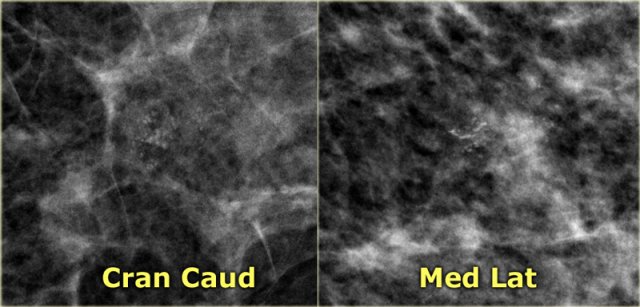

Milk of Calcium

These are benign sedimented calcifications in macro- or microcysts.

On craniocaudad views they appear as fuzzy, round or amorphous.

Consider magnification spot film with horizontal beam when you think of the possibility of milk of calcium, because on a 90? lateral view they may appear as semilunar, crescent shaped tea cups.

Many calcifications representing milk of calcium within microcysts however do not layer on horizontal beam radiographs.

The most important feature of these calcifications is the apparent change in shape of the calcific particles on different mammographic projections (craniocaudal versus oblique or 90? lateral).

The images show a different shape on the oblique view compared to the mediolateral view.

On the mediolateral view there is layering of the calcium.

On the craniocaudal image the calcifications are round, fuzzy and ill-defined.

On the mediolateral view the calcifications appear as semilunar, crescent shaped tea cups.